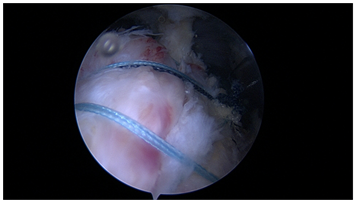

A promising technique for small or partial tears (PASTA) is a single tunnel repair (Figure 3). As demonstrated, this repair can create excellent coaptation of the tendon, with added strength from suture grasping stitches. A single tunnel in small repair area can provide “2 for 1” fixation points relative to a single anchor with a true transosseous, circumferential stitches rather than a transosseous equivalent construct with multiple anchors. It is likely that lateral anchors in this clinical situation add little value relative to their cost.

Figure 3 Single tunnel repair for a small rotator cuff tear.